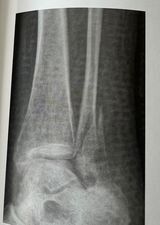

Hvad viser røntgenbilledet?

Der ses lateral malleolfraktur med mindre subluksation af talocruralleddet. Ingen fraktur af mediale malloeol, ingen mistanke om syndesmoseruptur.